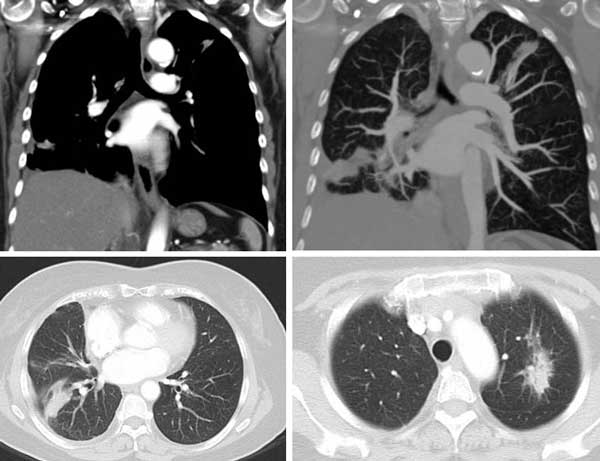

Meaningless shrinkage of tumour by Iressa

Meaningless shrinkage of tumour by Tarceva

These two cases happened with patients in Jakarta (above) and in Malaysia (below). And this also happened some years later with Dr. Paul in Stanford. What can we learn from such cases?